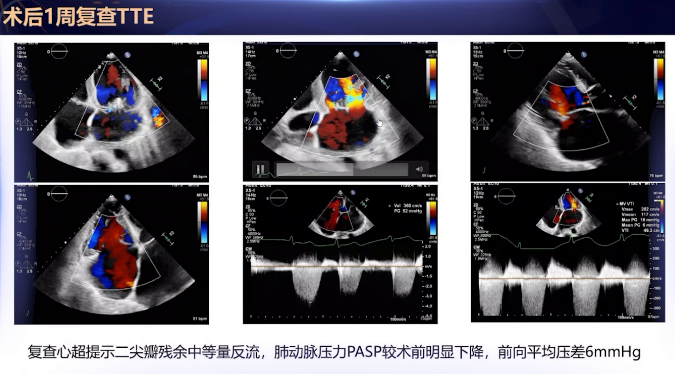

术后恢复:术后次日即可下床活动,胸闷、气促症状及活动耐量明显改善。术后一周复查超声心动图提示:二尖瓣残余中等量反流,肺动脉收缩压降至52 mmHg(术前78 mmHg),二尖瓣平均压差6 mmHg。患者顺利出院。